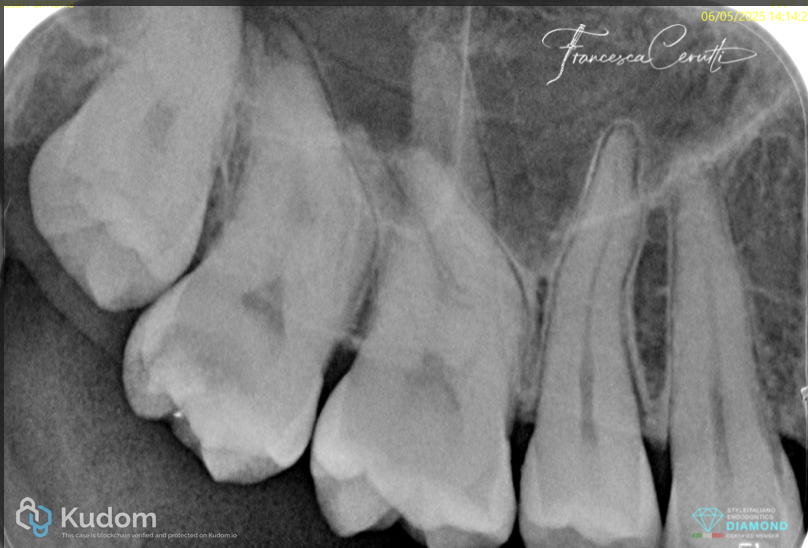

Fig. 2

The pre operative X-ray showed the curved anatomy of the tooth